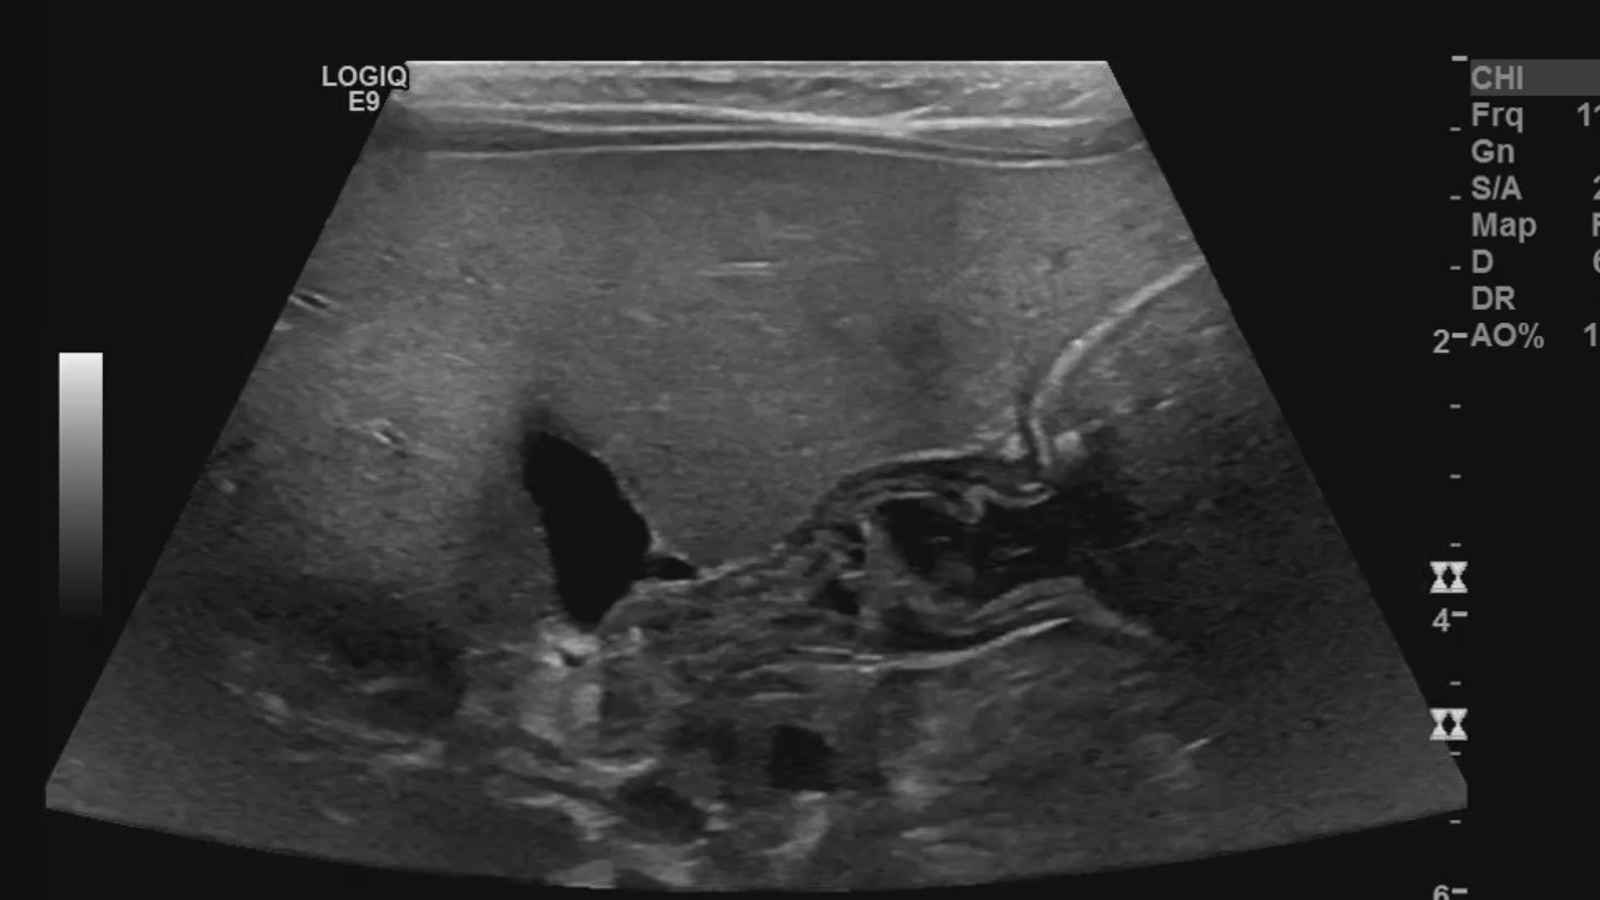

image1